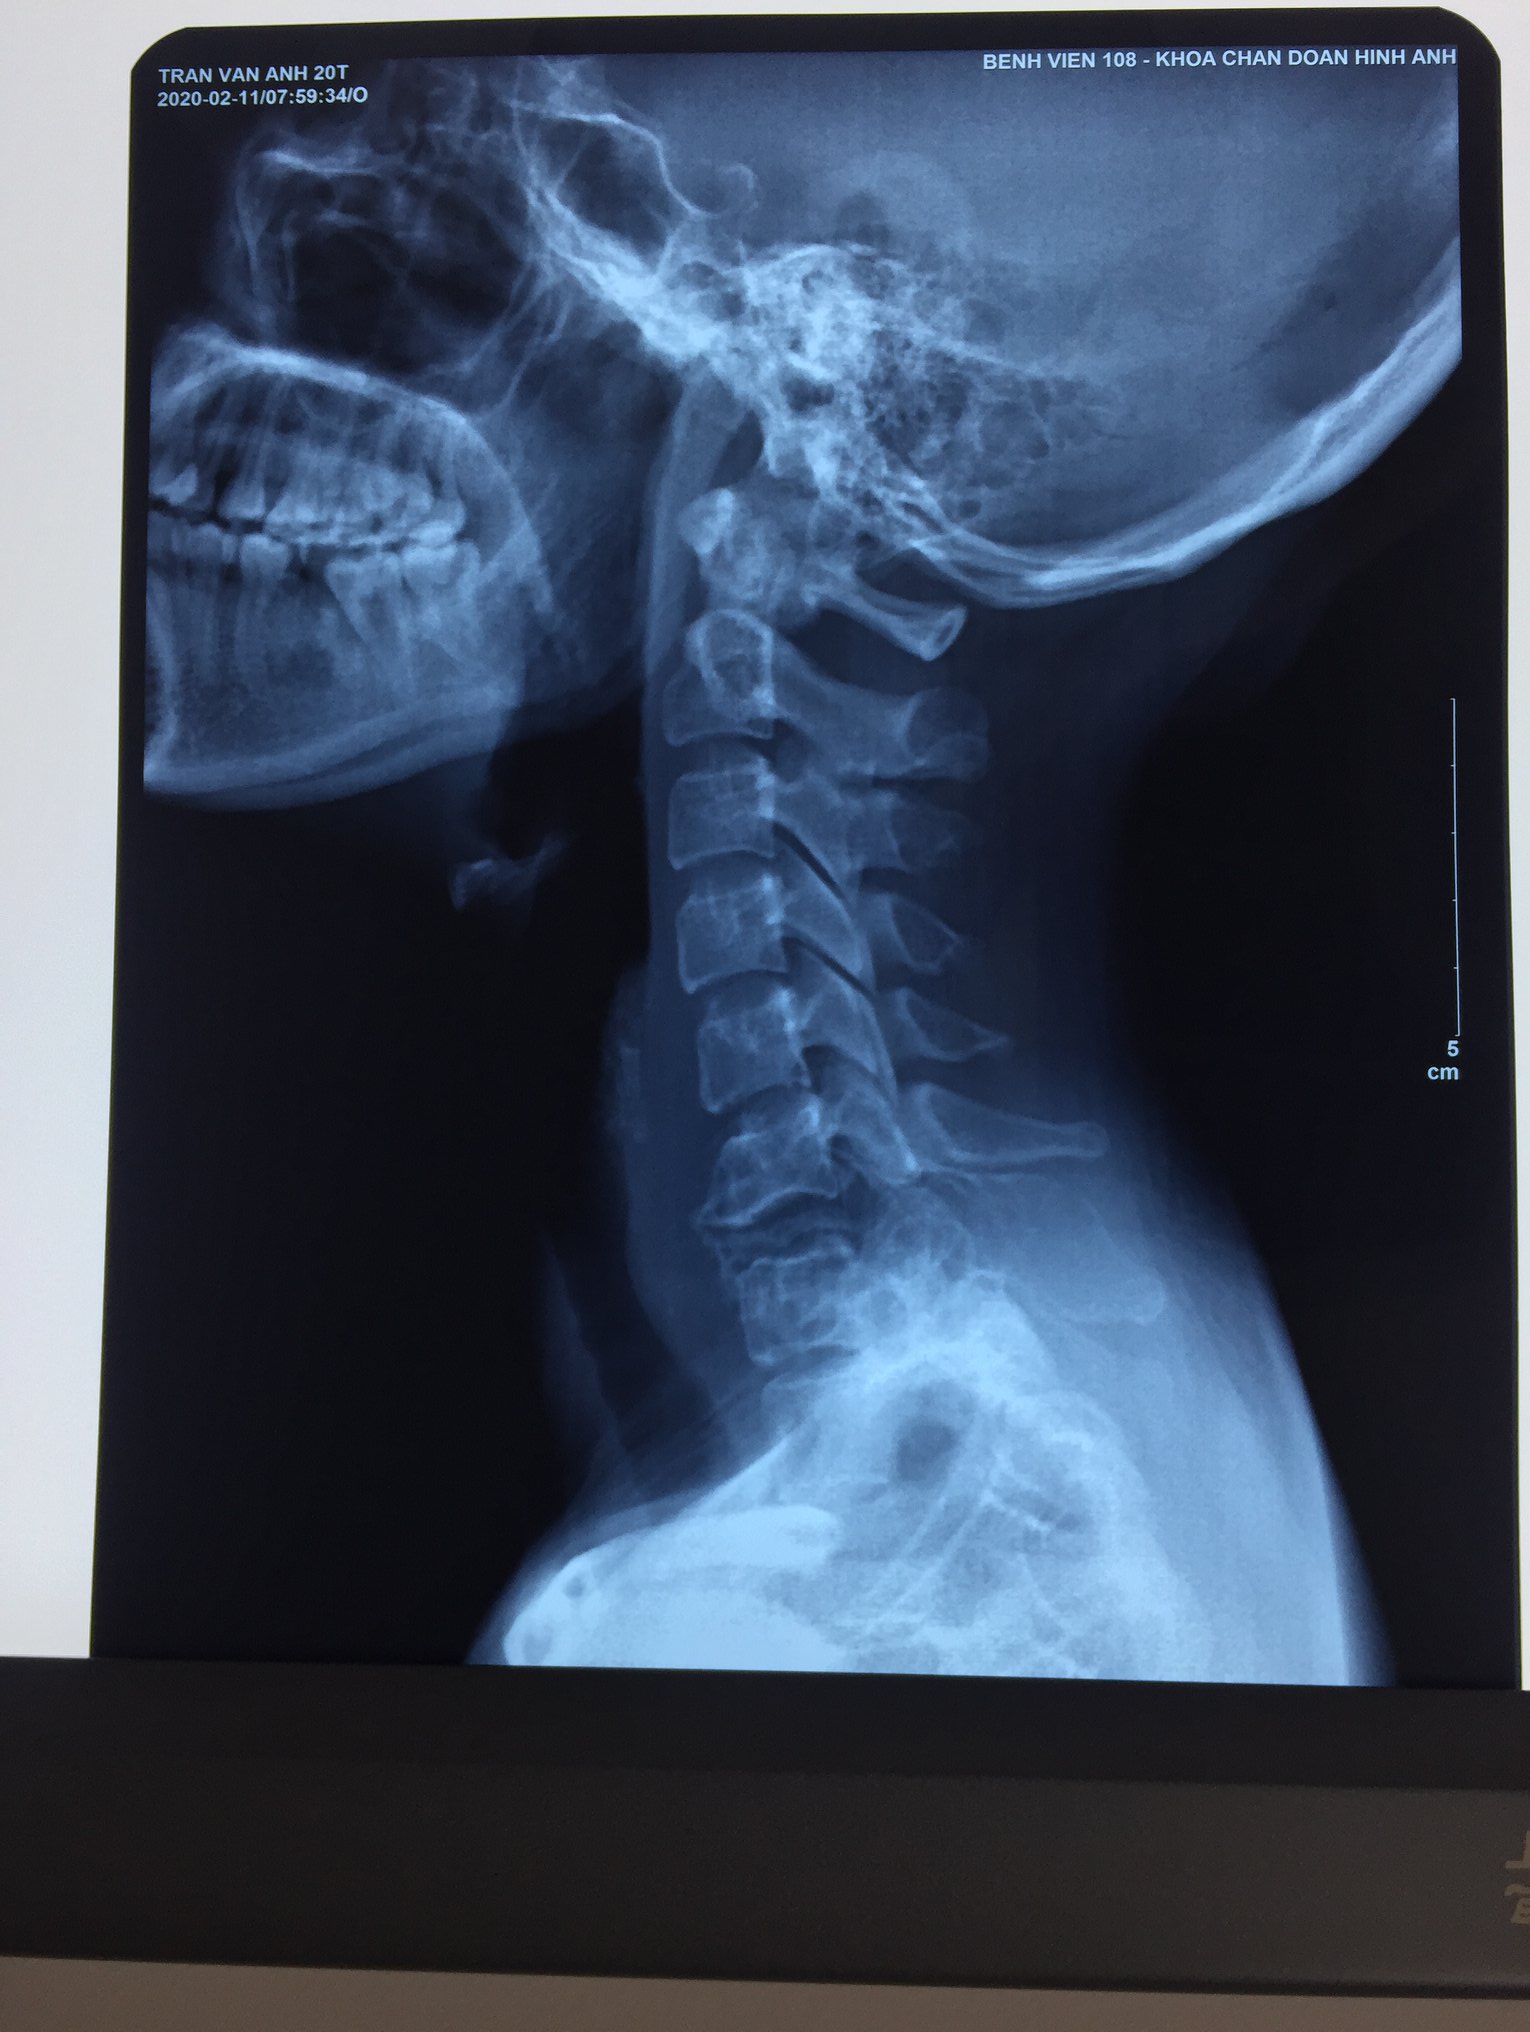

Chúng tôi xin giới thiệu trường hợp anh bệnh nhân Triệu Minh L. 36 tuổi bị bệnh viêm cột sống dính khớp 15 năm nay. Suốt 5 năm gần đây, anh luôn bị đau thắt lưng rất nhiều, đau nhất khi thay đổi tư thế và khi đi lại. Anh đi khám chữa bệnh nhiều nơi nhưng không khỏi. Chỉ khi anh gửi phim cho bác sĩ Hậu, trưởng khoa Chấn thương Chỉnh hình Cột sống, Bệnh viện Trung Ương Quân đội 108, anh mới biết mình bị bệnh: khớp giả đĩa đệm và cột sống T11-T12, mất vững cột sống và có chỉ định phẫu thuật. Anh và gia đình đã bay từ Cần Thơ về thủ đô Hà Nội để điều trị bệnh trong tháng 11.

Các bác sĩ đã tiến hành phẫu thuật cố định cột sống qua cuống T9-L3, cắt 1 phần thân đốt T12 và ghép xương liên thân đốt T11-12.